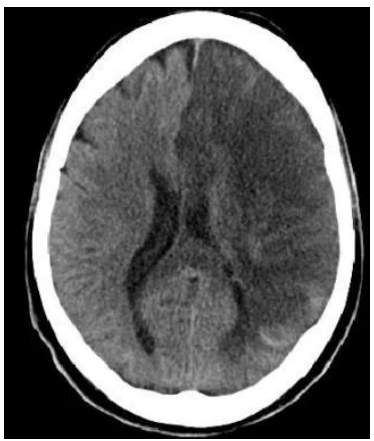

Sobre o manejo de pacientes com traumatismo crânio-encefálico

(TCE), é correto afirmar que

Paciente feminina de 57 anos, hipertensa e diabética tipo 2

insulino-dependente com tratamento irregular, admitida no

pronto socorro há 36 horas por acidente vascular encefálico

isquêmico em topografia de artéria cerebral média esquerda, fora

de tempo de trombólise.

Durante o seu plantão, a paciente evolui com rebaixamento do

nível de consciência e é entubada para proteção de vias aéreas. Ao

exame físico pós-intubação, encontra-se em RASS -5 sem

sedoanalgesia contínua, com anisocoria esquerda > direita,

mantendo hemiplegia dimidiada à direita, pressão arterial de

200x120 mmHg, FC de 65 bpm, ventilando em modo controlado,

bem acoplado e sem assincronias, com ausculta cardíaca e

pulmonar sem alterações.

Exames laboratoriais pós intubação evidenciando Hb 12.2, Ht 36,

leucócitos 9500, plaquetas 240.000, Ur 40, Cr 1.2, Na 132, K 4.2,

Mg 1.9, pH 7.30, pCO2 58, pO2 130 e HCO3 23.

Tomografia computadorizada de crânio sem contraste, com

hipodensidade fronto-parieto-temporal volumosa à esquerda,

apagamento de sulcos e desvio contralateral da linha média.